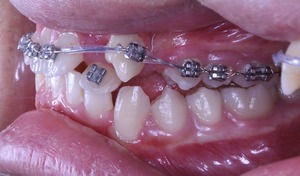

歯を動かすということは、隙間がないと不可能です

なので、まずは犬歯を動かすことができる状況になるようにします

アプローチの仕方は先生によって様々ですが、 大切なことは 上記の注意事項をまもっておこなうことです。

現在の状況はもう少し治療が進んでいるのですが、矯正歯科ネットユーザー様からの質問が昨日でしたので、数か月前の記録ですが、現在の進行状況です

正面と側面の写真をみてもあまり変化がわからないと思います。